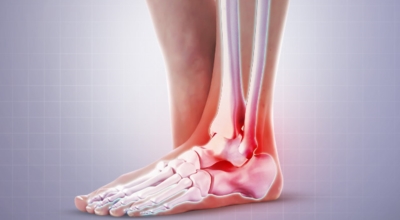

족저 근막이란 발가락 시작지점부터 발뒤꿈치뼈까지 발바닥 전체를 감싸고 있는 두꺼운 막을 말합니다. 족저 근막은 발바닥 아치를 지속시켜 발바닥이 지면을 내딛음으로써 발생하는 충격을 흡수하는 중요한 역할을 수행하고 있답니다. 이 족저 근막에 일차적으로 서서히 조직 손상이 일어나고 계속적인 활동으로 말미암아 염증이 커지면서 발 뒤꿈치 부근 통증을 일으키게 되는데 염증은 무리하고 반복적인 동작, 많은 사용으로 마찰에 의해 발생합니다.

족저 근막염은 염증에 의한 손상 및 통증을 유발하는 질환인데요 족저 근막염 증상은 일반적인 발뒤꿈치 통증 하글런드 병변의 기형으로 알려져 있으고 아킬레스 건과 관련이 깊다고 합니다. 특히 근육이 덜 풀린 아침 시간 대는 보행 시 날카롭고 바늘로 찌르는 듯한 심한 통증을 느끼게 된다고 합니다. 하지만 아침 시간 대를 지나 오후에 접어들면서 어느 정도 통증은 서서히 감소하기 시작한다고 하는데요 초기 증상이 나타난다면 꼭 전문의를 찾아 조기치료하는 것이 바람직합니다.